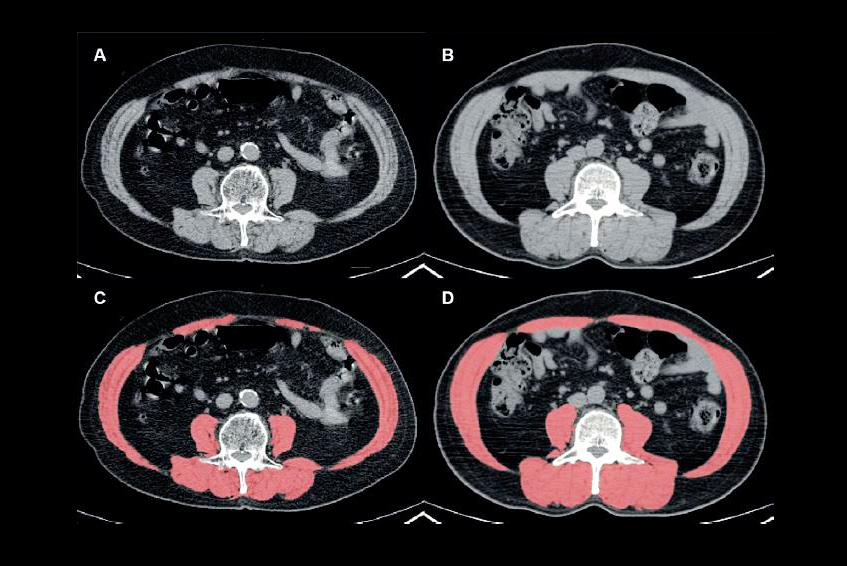

Image courtesy of Dr. Bari Dane.The takeaway? CT provides important data for predicting COVID-19 severity in obese patients that go beyond the basic BMI measure, according to Dane.

Understanding whether a COVID-19 patient's adipose tissue is subcutaneous or visceral is important, said presenter Dr. Bari Dane of NYU Langone Medical Center in New York City.

"Fat deposits are not all equal," Dane told session attendees. "[We found levels of] visceral adipose tissue and muscle adipose tissue significantly different in COVID-19 inpatients versus outpatients."

Obesity is typically measured by the body mass index (BMI) formula, which calculates a score based on a person's tissue mass (muscle, adipose, and bone) and height. BMI offers a broad picture of a patient's health, but body composition is actually more nuanced, Dane said. She and her colleagues explored whether visceral or subcutaneous fat visualized on CT correlated with COVID-19 disease severity and/or with BMI via a study that included 51 patients (10 outpatients, 30 people hospitalized but not ventilated, and 11 individuals who were both hospitalized and ventilated).

Dane's group found that the presence of higher levels of visceral fat translated into a statistically significant increase in the severity of COVID-19 -- a result that did not correlate with individuals' BMI scores, which suggests that BMI is a less useful measure for predicting hospitalization (subcutaneous fat did not have this same association but had a strong correlation with BMI). The same was true for muscle: Higher levels of muscle fat were significantly linked to increased COVID-19 severity (p<0.001).